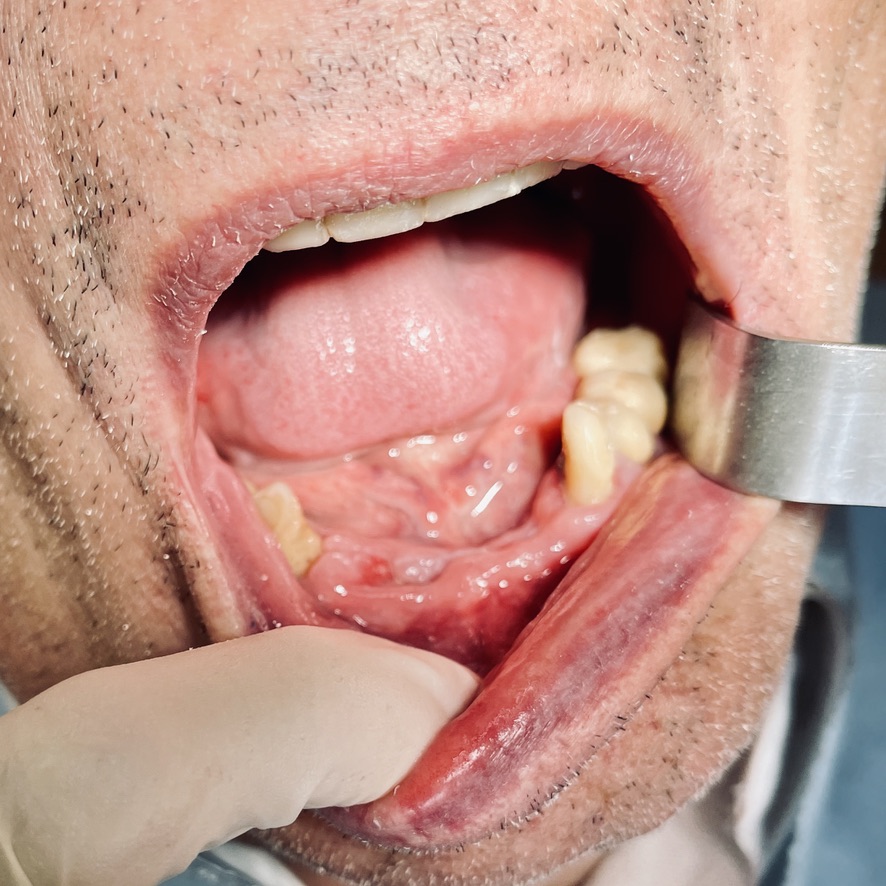

CASO CLINICO : Riabilitazione del 28/04/2021

In particolare considero notevoli i seguenti aspetti:

• 10 grave parodontopatia del settore inferiore

• 11 problematiche igieniche

• 12 insuccesso implantare di impianto di Tramonte inferiore, impianto precedente al 2004, nel quadro della generale parodontopatia

Le immagini forniscono nelle didascalie ulteriori informazioni.